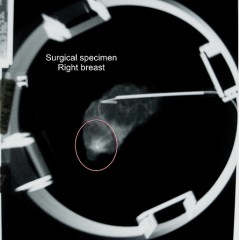

The hospital where I worked still used film-screen technology then. So, after my co-worker performed the exam at the end of the day, I waited with her by the film processor and watched as

she hung up each film. And there, right next to my chest wall was a tiny, spiky lesion that was not there on prior exams. I knew from having seen other lesions like it that it was most likely cancer, and my heart dropped.

The radiologist said he was 80% sure it was going to come back positive for cancer but he wanted additional imaging before he suggested a biopsy. On June 21, 2007, I had a diagnostic mammogram that confirmed the radiologist’s suspicions. He recommended a biopsy.

Because I work in a hospital that performs breast needle localization procedures and biopsy, my doctor and radiologist worked with the surgeon and got me on the OR schedule for the following week. And on July 3, 2007, I got the confirmation I had been dreading. I had breast cancer.